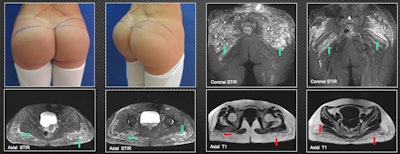

MRI provides the most information to the radiologist and should be done on all patients, they stated. "It can warn the surgeon about the level of tissue compromise. It shows the affected planes and the approximate amount of biopolymers injected. It demonstrates their areas in the case of material migration."

Additionally, MRI presents the biopolymer in encapsulated form (rounded-oval or elongated vesicles). The round and elongated vesicles can be seen affecting the subcutaneous cellular tissue, so the location is superficial, while the elongated ones are found on deep planes, infiltrating the gluteal fibers.

A few weeks after placing the biopolymers, liquid forms can be seen that simulate seromas without vesicles. After six to 12 months, seromas and vesicles coexist. After more than 18 months, only vesicles containing the biopolymer material are found. In many patients, there is migration from deep to superficial planes, which, due to their shape and distribution, suggests that lymphatic drainage has occurred.

The length of time that patients carry the biopolymer in the buttocks plays an important role in the way the material will be presented in tissues, the authors wrote.